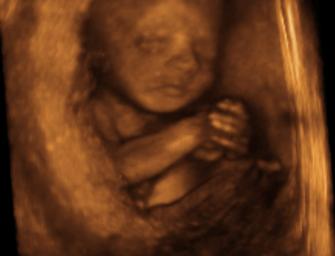

Sonogram of baby at 26 weeks